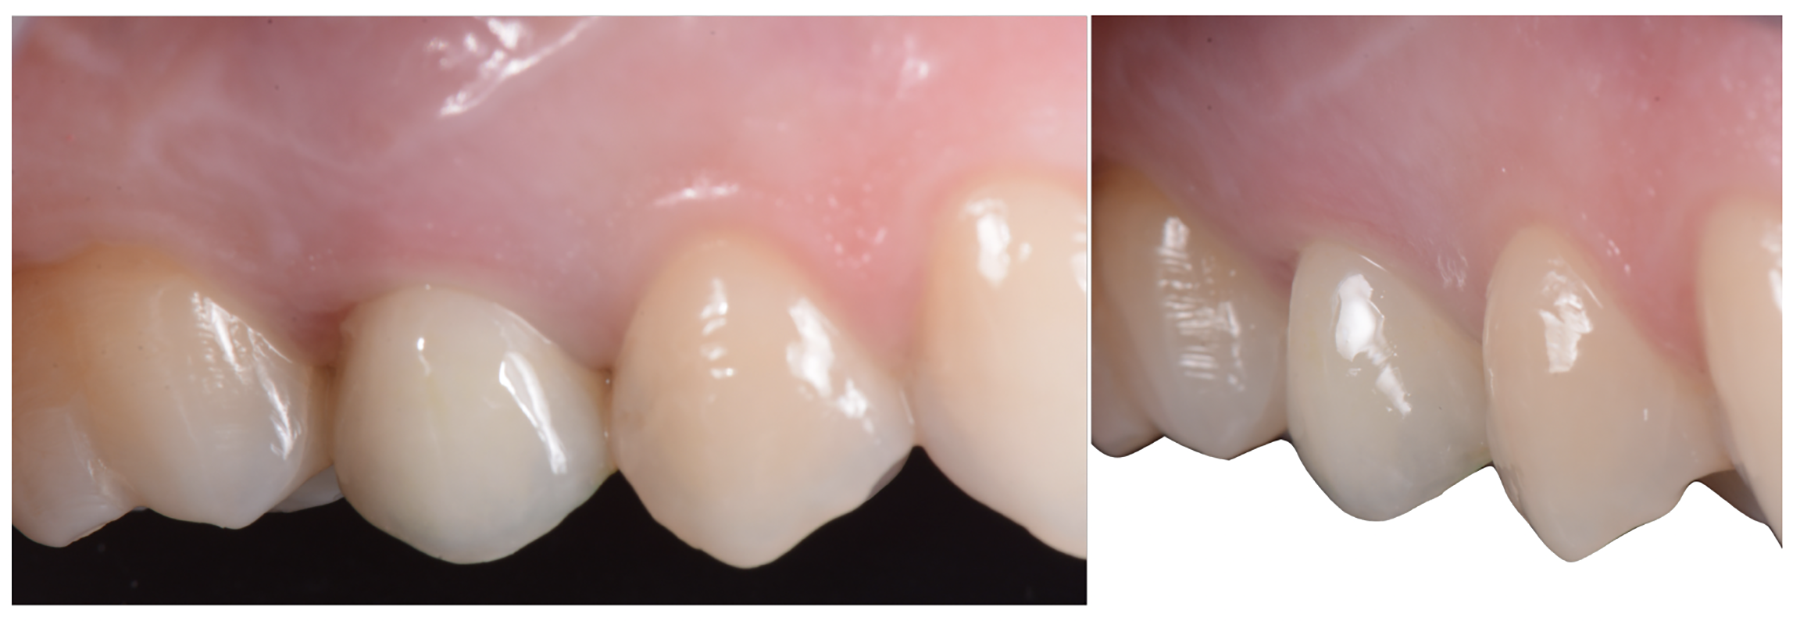

Tissue integration also depends on the surface properties of the materials in contact with peri-implant tissues, such as the surface energy and the decontamination and sterilization of the surfaces. Customized Computer-Aided Design/Computer-Aided Manufacturing (CAD/CAM) titanium and zirconia abutments may be fabricated using multiple technical procedures, all of which inevitably contaminate the surfaces of the materials, thus potentially compromising soft tissue integration and adherence.32 In vitro results have suggested that the decontamination of abutment surfaces is important for early fibroblast adherence and may improve the biological integration of peri-implant soft tissues.29 Ideally, abutments should have a surface that is completely decontaminated and sterilized, so as to allow for tight soft tissue adherence and integration in the subcritical and critical zones to support peri-implant tissues as well as create an effective soft-tissue seal/defense area against bacterial microorganisms. To achieve the best clinical performance in terms of soft tissue adherence, stock final abutments that are completely decontaminated and sterilized, with surface chemistry that boosts their biological response, should be the first choice (Figure 3 and Figure 4). These abutments are available in multiple heights, which should be selected based on the implant site, the vertical soft tissue thickness, and the esthetic expectations.

The critical contour should be designed to correctly support the soft tissues, conditioning and scalloping the pink esthetics. The height of the aCA should range from 2 to 2.5 mm (Figure 2), depending on the esthetic demands of the individual clinical case. In this area, particularly in the most coronal portion, the cleanability of the abutment is crucial to reduce the risk of contamination, and therefore a thoroughly polished surface with mirror-like appearance is necessary. This is particularly important in patients with poor or suboptimal oral hygiene, with a history of periodontal disease, or who smoke.

Finally, once the proper 3D position of the implants has been identified, the abutment placement protocol to be used should be evaluated. The "one abutment/one time" approach4,6,8,17 allows soft tissues to adhere firmly onto the surface of titanium abutments, thereby improving soft tissue response and bone stability (Figure 4 and Figure 7 through Figure 14 ). This approach avoids multiple connections and disconnections at the bone interface and favors undisturbed bone and soft tissue healing.4-7